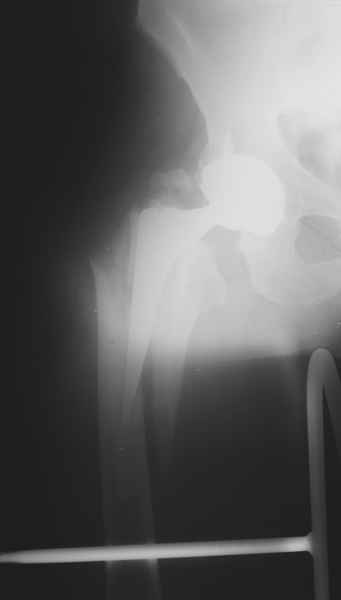

Хочется показать два подобных случая, П-ка З. 72 лет и п-т Г. 80 лет. Сразу принимаю замечание, что это были ножки цементной фиксации, просто под руками не было бесцементника.

2. Применение ножки дистальной фиксации, мы отдаем предпочтение ножке Вагнера с фиксацией проксимального отдела на ножке. Более травматичное вмешательство, но при стабильной фиксации ножки реабилитация идет в обычном режиме.